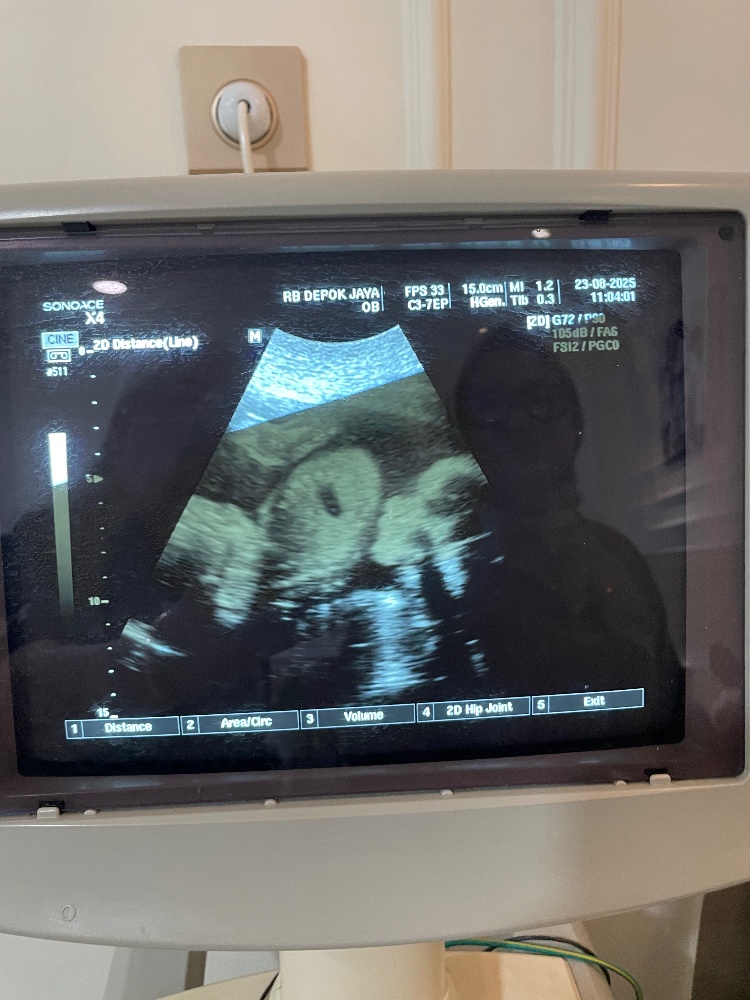

助産院ではエコーで赤ちゃんのお腹の様子も見せたりしていて、みんなエコー好きですよね。

確かに指しゃゃぶりする様子が見れたりするとかわいいから、やっぱり見たいのですね。

インドネシアの助産師さんはエコーするのもライセンスが必要で、ここ最近のインドネシアの助産師さんの動向を見ていると、エコー出来る助産師はステータスになっています。